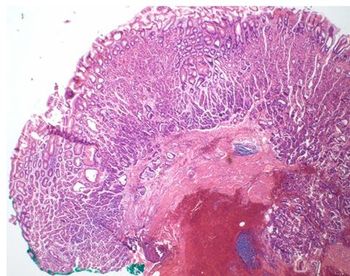

A young woman with a history of a desmoid tumor as a child undergoes a screening colonoscopy. What gene mutation is suggested by the finding of multiple adenomatous polyps?

Fundic gland polyps are the most common form of gastric polyps. Giant FGPs, however, are extremely rare.